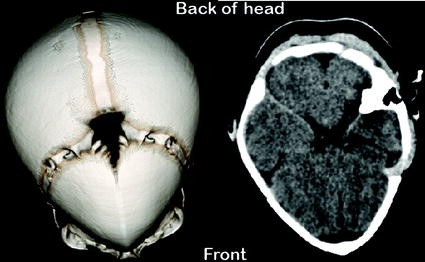

Normal Brain Ct Scan Hydocephalus